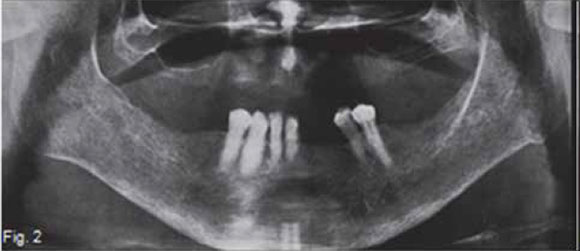

Below are images of a condition caused by a deficiency of organic bone matrix; however, there is normal mineralization of the remaining bone. This condition is a common disorder affecting post-menopausal middle-aged women .What are the important radiological findings and diagnosis?

A figure 1 and 2 are pantomograhs of two elderly woman shows thinning of the cortex at the inferior border at the angle of the mandible. There are cortical laminations with endosteal detachment. The alveolar bone is denser (darker) than normal, although the teeth are exposed correctly; trabeculae are fewer in number, coarser and showing reduced density. Figure 3 of another patient shows a classic appearance of the same condition in the vertebral column; loss of horizontal trabeculae; thicker, more prominent vertical trabeculae; and more radiolucent vertebral body (red arrow). The posterior vertebral plate is coarser, with irregular endosteal surface. There is a wedge-shaped deformity of the disk, as can be seen by the V-shape of the intervertebral space (green arrow). In several places there is complete loss of the intervertebral space. A diagnosis of osteoporosis was made in all these cases. Figure 4 demonstrates changes from normal bone (a) to severe osteoporosis (b). Primary osteoporosis refers to a condition that is not associated with any of the diseases known to cause an osteoporotic state. No known causal condition has been established. According to Garn (1970), normal bone mass increases as a person progresses from infancy to 30 to 40 years of age and then decreases continuously at a rate of 8% per decade in women and 3% in men. This bone loss is particularly evident in the cortex and continuous until a person dies. Fifty percent of men exhibit cortical bone erosion by age 80; among women, 50% show cortical bone loss by the age of 70 and 100% by age 90. Trabecular bone is affected earlier than cortical bone, and the vertebral column is the prime site of advanced cases. In women osteoporosis results from increased resorption that is associated with menopause. During menopause, there is diminished production of oestrogens, which tend to protect the skeleton against the resorbing action of parathyroid hormone. In men primary osteoporosis may develop from diminished androgen production. It has been shown in aging men that parathyroid levels increase, yet urinary excretion of calcium decreased with age. It is presumed that there is an increased tubular resorption of ionic calcium resulting from mild secondary hyperparathyroidism.This calcium-saving mechanism is missing in women. Regardless of the cause, osteoporosis results in an increase of fractures in the axial skeleton and possibly tooth loss and alveolar ridge resorption in the jaws.